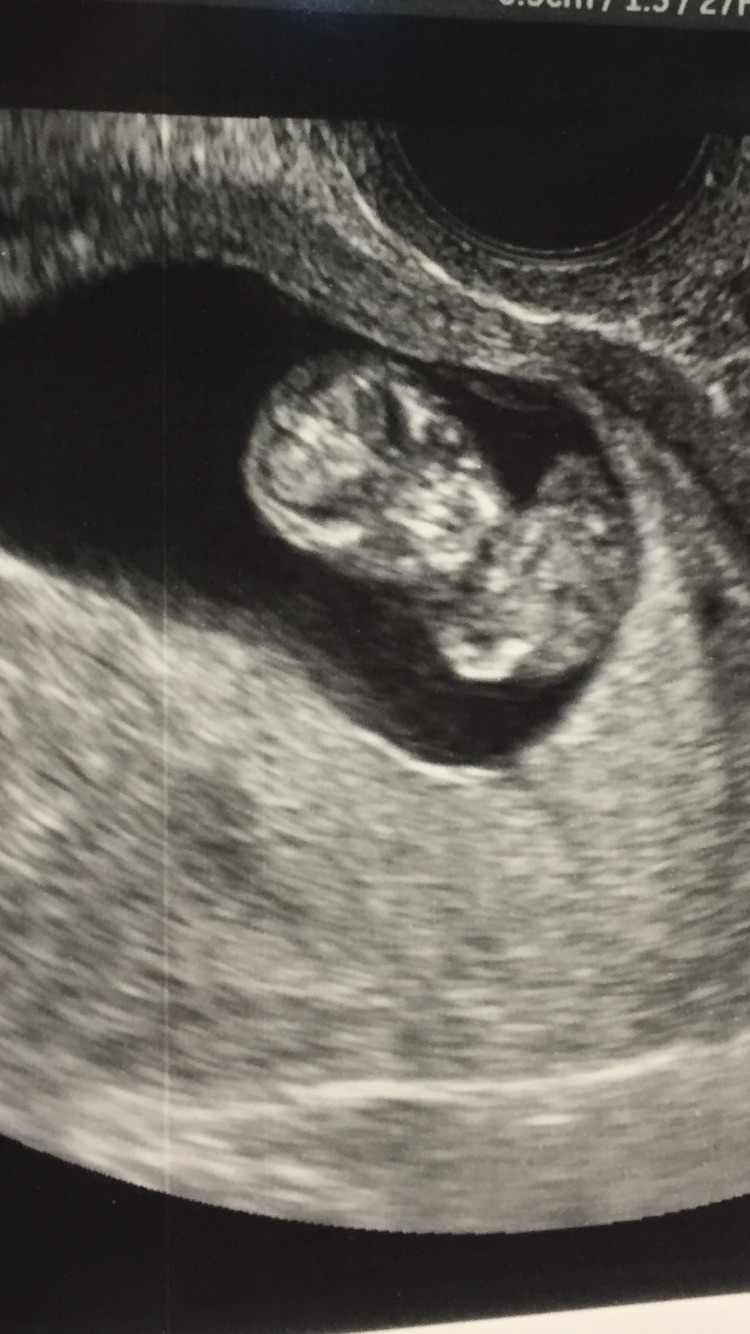

Sorry if this isn't what US post is for but I had to share. I posted my photo about a week ago from my NT scan. I've been on the edge of my seat waiting for the phone call for results. I'm 35 and DH is 53 so we were told we are already at increased risk. Finally got my call today! Fold measured at 1.37 and my risk level is 1 in 7500

Had my 12 week u/s and NT scan today! Baby is looking fab and is chillen' in the womb like a champ! So relieved and blessed to hear everything looks ok, we should receive the blood work results in 2 weeks.